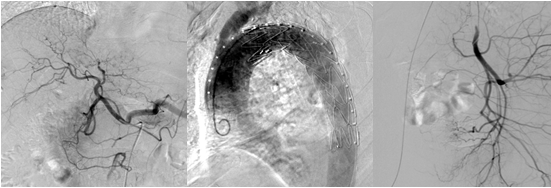

1.3 数字减影血管造影DSA

数字减影血管造影是上世纪80年代继CT之后出现的将电子计算机与常规X线血管造影相结合的一种新检查方法。近年来,选择性动脉造影得到广泛应用。DSA影像的形成是基于数字荧光成像DF,其影像形成过程与传统的利用X线成像相同,即透射成像。